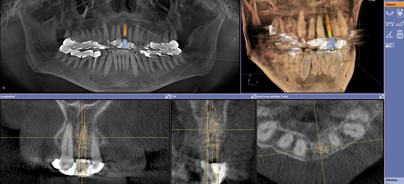

In unserer Klinik stellte sich ein 59-jähriger Patient mit Frontzahntrauma an Zahn 21 und 11 vor (Abb. 1). Mithilfe der integrierten Implantologie planten wir die Behandlung bereits vor dem eigentlichen Eingriff: Zunächst fertigten wir ein dreidimensionales Röntgenbild mit einem digitalen Volumentomografen (GALILEOS Compact, Sirona, Bensheim) an. Dabei stellten wir fest, dass der Zahn 21 aufgrund einer Querfraktur der Zahnwurzel entfernt werden musste. Mit dem CAD/CAM-Restaurationssystem CEREC (Sirona, Bensheim) erstellten wir dann den prothetischen Vorschlag und importierten diesen in das DVT-Datenmaterial mittels Implantat-Planungssoftware (GALILEOS Implant, Sirona, Bensheim). Dazu markiert der Anwender sowohl bei den CAD/CAM-Daten als auch im 3-D-Röntgenbild einander entsprechende Punkte, sodass die Software die beiden Datensätze exakt überlagern kann (Abb. 2). Im vorliegenden Fall stellten wir bei der virtuellen Implantatplanung fest, dass die Knochenwand lingual nicht stark genug für eine Implantation war. Nach der Entfernung des avitalen Zahns 21 sowie der Wurzelreste führten wir deshalb eine chirurgische Socket Preservation mit einem Granulat (Cerasorb® M, curasan AG) durch. Darüber hinaus versorgten wir den Zahn 11 mit ­einer Kunststofffüllung und schienten den gesamten Frontzahnbereich, um die Zähne in ihrer Position zu ­stabilisieren. Nach acht Wochen setzten wir das Implantat (ICX-Implantat, medentis medical) zur Osseointe­gration. Nach drei Monaten legten wir dieses mittels W-Plastik frei (Abb. 3). Für die Krone in Regio 21 fertigten wir ein Kiefermodell aus einem scanbaren Gips an und konstruierten mithilfe dessen den prothetischen Vorschlag. Da in dem vorliegenden Fall keine Bohrschablone eingesetzt wurde, haben wir dieses Verfahren gewählt, um nach der Implantation die optimale Position der Restauration festzulegen. Die finale Versorgung nahmen wir jedoch mit CEREC vor: Den von uns virtuell konstruierten prothetischen Vorschlag passten wir den Erfordernissen dieses Falls entsprechend an und schliffen die Restauration mit der CEREC MC XL-Schleifmaschine mit der VITABLOCS® TriLux Keramik aus. Der Zahn wurde anschließend noch individualisiert und glanzgebrannt. Die Krone wurde dann auf dem Abutment mittels Panavia®-Zement definitiv eingegliedert (Abb. 4).